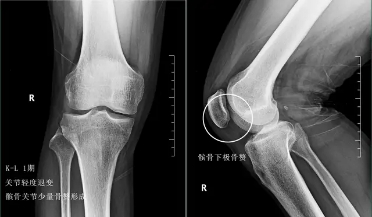

前面已经说到骨关节炎会导致骨赘的形成以及关节间隙的狭窄,所以我们依靠膝关节x片子来初步判断骨关节炎的病情,通常我们采用K_L分期判断病情。

二期患者:2期的患者关节的那个骨赘就已经开始明显增多了,但是这个时期关节的间隙仍然不会发生狭窄,这就说明关节内的软骨虽然已经有了磨损,但是磨损的程度还可以,不是特别的重。

往往这个时期的患者,如果症状比较明显,在医院检查发现了骨关节炎,治疗起来反而效果最好。因为关节的软骨还没有磨损的特别严重,此时我们通常可以采取给于关节内进行玻璃酸钠、几丁糖或者是富血小板血浆因子注射的办法来减缓软骨磨损的进程,缓解患者的症状。此时也可以给予患者口服氨糖。